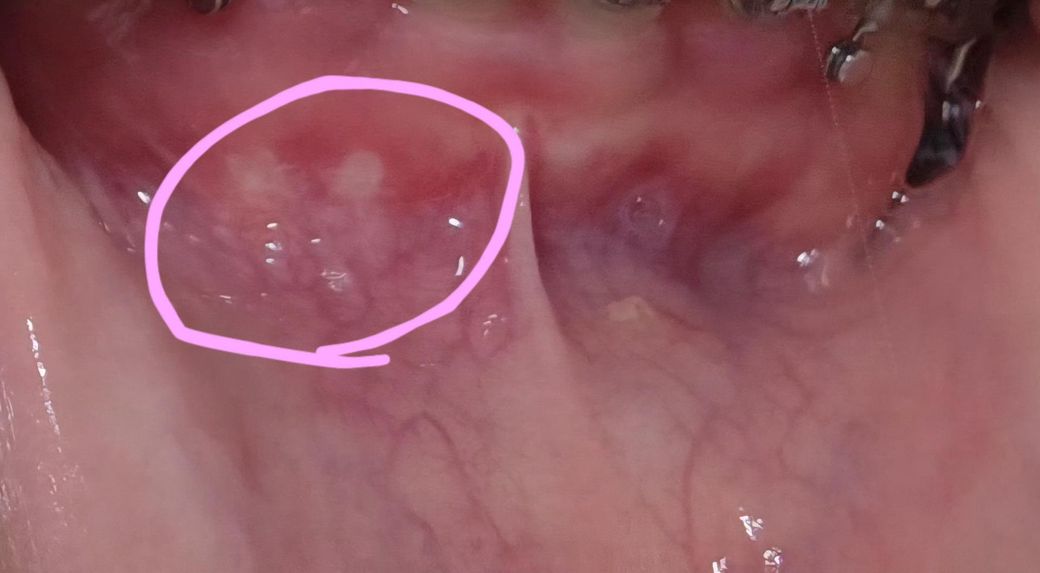

잇몸에 염증이 난걸까요 누르면 너무 아파요....

핑크색 동그라미 친 부분을 누르면 너무 아파서

이게 무슨 염증이 난건지 모르겠습니다..

• 1번 째 사진

사진상에 보이는건 자극을 받아서 구내염이 생긴거 같습니다 큰 문제가 잇는건 아니니 너무 걱정하지마세요.

잇몸 부위 흔하게 나타나는 구내염 양상으로 보입니다 오라메디 약국에서 사서 도포해보세요